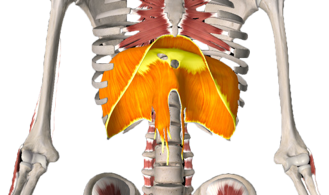

Samentrekkende psoasspieren laten het lichaam vooroverbuigen. Gespannen of beschadigde psoasspieren kunnen hevige pijn in de onderrug veroorzaken. Dit komt bijvoorbeeld veel voor bij mensen die seksueel misbruikt zijn. Secundaire rugpijn of beenpijn ontstaat hier veelal bij, doordat het lichaam probeert de voorwaartse trek van het lichaam te compenseren. De lange rechte rugspieren trekken het lichaam naar achter in een poging het staande te houden. Hierdoor ontstaat er spanning op de ruggenwervel, wat op den duur chronische schouder- en nekklachten tot gevolg kan hebben. Daarnaast kan de middenrifspier ook spanning in dit gebied veroorzaken.

Om te herstellen van fysieke traumatische spanningen moeten vooral de diepliggende psoasspiergroep, de spieren waarmee je de rug strekt (de erector spinae) en de schouder- en nekspieren hun defensieve spanning weer loslaten en terugkeren in de ontspannen toestand.

De spieren die bij stress vooral samentrekken zijn:

4. Middenrif

5. Vierhoekige lendenspier

4

5